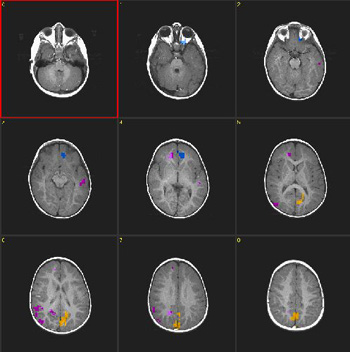

Niño de 18 meses de edad con parálisis cerebral leve. |

ACTIVADO: Presentación de la voz de la madre, pregrabada, en la que usa palabras y sonidos familiares

DESACTIVADO: Nada. Paciente sedado con propofol |

| Prueba T |

0,0005 |

3,2 |

| Activación |

La activación de las áreas auditivas está bien definida. Se observa activación bitalámica. No se comprende claramente la fuerte activación del lóbulo frontal parasagital derecho. |